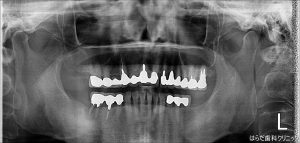

オペ前とオペ後のレントゲンの写真です。

しっかりと埋入されています。

この後骨に定着するのを数か月待ちます。